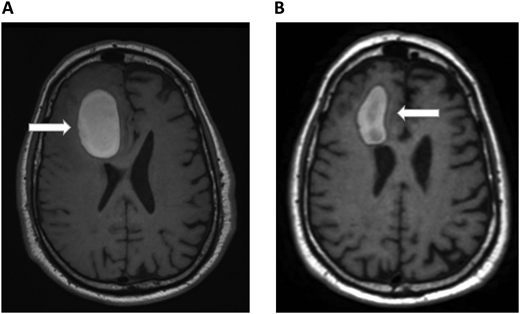

A 72-year-old man with a history of metastatic melanoma presented to the emergency room with new confusion and aphasia. He had been treated with ipilimumab and nivolumab 1 year earlier with complete remission and had known brain metastases treated previously with stereotactic radiosurgery. A brain MRI scan revealed significant frontal intraparenchymal bleeding with surrounding edema, consistent with bleeding brain metastases (Figure 2A). He was admitted to the oncology ward and showed gradual clinical improvement with conservative management. Positron emission tomography CT revealed relapsed systemic disease with liver metastases. Pneumatic graduated compression stockings were used for DVT prophylaxis. On the seventh day of admission, he developed dyspnea. His vital signs were notable for the following: blood pressure, 140/70 mm Hg; pulse, 120 beats/min; respiratory rate, 28 breaths/min; and pulse oximetry, 88% on room air. CT chest PE protocol revealed a new left lobar and segmental pulmonary embolus. His platelets, renal and hepatic function, and partial thromboplastin time and prothrombin time were normal. Echocardiogram did not show right heart strain. Hematology was consulted on the management of a patient with bleeding brain metastases and acute PE. He underwent repeated brain MRI scans that showed improvement in the size of the bleeding and mass effect (Figure 2B). Since the ICH volume was greater than 10 mL, we considered him to be at high risk of ICH expansion and did not consider him to be a candidate for therapeutic-dose anticoagulation in the foreseeable future. We therefore recommended placement of an inferior vena cava (IVC) filter. Because his ICH was 7 days early and was improving clinically and on imaging, we recommended prophylactic-dose enoxaparin. The decision to allow prophylactic-dose anticoagulation is extrapolated from the spontaneous ICH literature that suggests that prophylactic dosing of unfractionated heparin or LMWH can be safely administered within several days of ICH diagnosis.25 For example, retrospective studies demonstrated the safety of initiating LMWH prophylaxis within 48 hours of admission for ICH.49,50 Therefore, when indicated, we consider prophylactic dosing of either unfractionated heparin or LMWH within 2 to 4 days following the diagnosis of ICH. The rationale for prophylactic-dose anticoagulation in this patient is to prevent IVC filter thrombosis and PE progression.

Brain MRI in a patient with melanoma and hemorrhagic brain metastases. In Panel A, an axial section of a T1 image without contrast shows a right frontal hemorrhage (5 cm × 3 cm) with mass effect. In Panel B, a T1 image with contrast demonstrates improvement in the right frontal hemorrhage (3.5 cm × 2 cm) and its mass effect. The white arrows denote these findings.